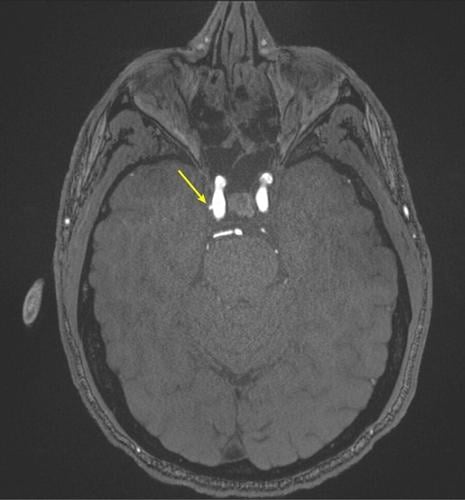

Representative axial time-of-flight MR angiography image in a 39-year-old male participant shows a laterally projecting intracranial aneurysm (arrow) originating from the right cavernous segment of the internal carotid artery. (RSNA via SWNS)

Representative axial time-of-flight MR angiography image in a 35-year-old male participant shows a medially projecting intracranial aneurysm (arrow) originating from the right cavernous segment of the internal carotid artery. (RSNA via SWNS)

Among all evaluated MRI findings, only intracranial aneurysms were associated with cumulative blast exposure.

Aneurysm prevalence was greater in the high-exposure group (9.5%) compared to the low-exposure group (2.7%).